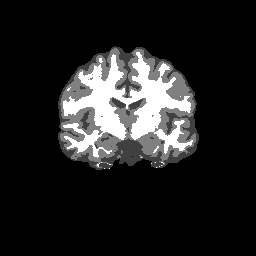

Accuracy is reported as Dice overlaps between a tool's segmentation and the Internet Brain Segmentation Repository (IBSR) manual segmentation for each of the 18 IBSR subjects. The inter-tool comparison (on the left below) shows the median Dice coefficient for each tissue class. The overlaps for FSL (from which the median values are drawn) are shown in the plot on the right.